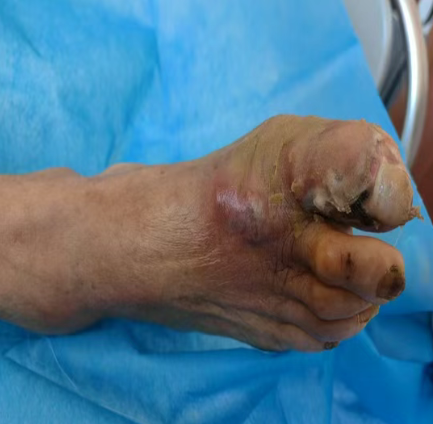

“剪个趾甲,没想到差点烂掉一只脚!”60岁的郭大爷患糖尿病8年,半月前剪趾甲时不小心弄破左足大脚趾。郭大爷没当回事,自行在家简单换药,可创面却越烂越大,甲周皮肤溃烂流脓,疼得连路都走不了。

治疗前

家人赶紧送他到青岛西海岸新区中医医院内分泌科求助,科室医生迅速完成全身及足部评估,制定个性化方案,通过精准清创、规范换药,及时遏制了病情发展。

治疗后